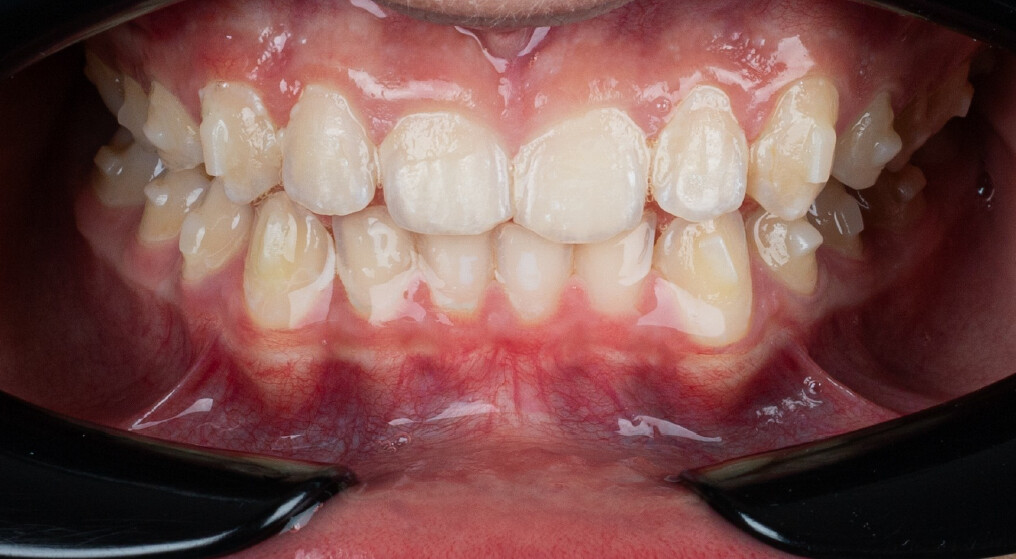

A 13-year-old male patient presented with a deep bite, characterized by near-complete coverage of the mandibular incisors. Clinical evaluation revealed bi-arch crowding, dental rotations, and proclination of the maxillary lateral incisors, contributing to the patient’s esthetic concerns. The facial profile was retrusive, consistent with mandibular retrognathism, and no significant periodontal abnormalities were detected.

The patient presented with a skeletal Class II relationship with bilateral molar and canine Class II and a Class II division 2 dental pattern. The deep bite was associated with anteroinferior crowding and an accentuated Curve of Spee. Facial analysis revealed good symmetry, a slightly increased lower facial third, and a convex profile characterized by mandibular and chin retrusion. Lip competence was mildly reduced, with a decreased nasolabial angle and mentalis hyperactivity, all of which compromised overall facial harmony.

The treatment was carried out using Angel Aligner clear aligners, with strict adherence to periodontal biological limits. Both maxillary incisor intrusion and transverse expansion were carefully monitored throughout the process to prevent any periodontal compromise. Mandibular advancement was initiated directly from the 4th aligner using advancement blocks, eliminating the need for a preliminary pre-advancement phase. The patient was at the CS3 stage of cervical vertebral maturation, corresponding to the pubertal growth spurt, a biologically favorable period for condylar remodeling and skeletal adaptation. A total of 35 aligners with advancement blocks were used, followed by 10 additional aligners incorporating Class II elastics on Angel Buttons to finalize rotations and alignment. With weekly aligner changes, the overall treatment duration was approximately 45 weeks (10 months), aligning with the expected biological timeline for condylar remodeling. For mandibular anterior intrusion, the Frog Protocol combined with interproximal reduction (IPR) achieved complete leveling of the Curve of Spee.